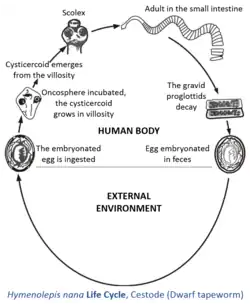

Infection is acquired most commonly from eggs in the feces of another infected individual, which are transferred in food, by contamination. Eggs hatch in the duodenum, releasing oncospheres, which penetrate the mucosa and come to lie in lymph channels of the villi. An oncosphere develops into a cysticercoid which has a tail and a well-formed scolex. It is made of longitudinal fibers and is spade-shaped with the rest of the worm still inside the cyst. In five to six days, cysticercoids emerge into the lumen of the small intestine, where they attach and mature.

The direct life cycle is doubtless a recent modification of the ancestral two-host life cycle found in other species of hymenolepidids, because cysticercoids of H. nana can still develop normally within larval fleas and beetles. One reason for facultative nature of the life cycle is that H. nana cysticercoids can develop at higher temperatures than can those of the other hymenolepidids. Direct contaminative infection by eggs is probably the most common route in human cases, but accidental ingestion of an infected grain beetle or flea cannot be ruled out. The direct infectiousness of the eggs frees the parasite from its former dependence upon an insect intermediate host, making rapid infection and person-to-person spread possible. The short lifespan and rapid course of development also facilitate the spread and ready availability of this worm.

Hymenolepis nana, like all tapeworms, contains both male and female reproductive structures in each proglottid. This means that the dwarf tapeworm, like other tapeworms is hermaphroditic. Each segment contains three testes and a single ovary. When a proglottid becomes old and unable to absorb any more nutrition, it is released and is passed through the host's digestive tract. This gravid proglottid contains the fertilized eggs, which are sometimes expelled with the feces. However, most of the time, the egg may also settle in the microvilli of the small intestine, hatch, and the larvae can develop to sexual maturity without ever leaving the host.